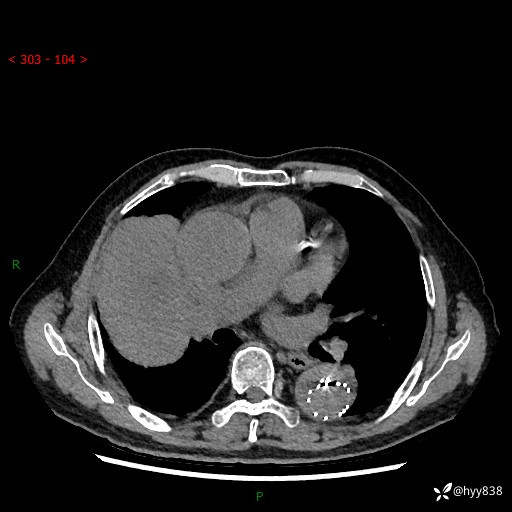

辅助检查:CT

静脉期